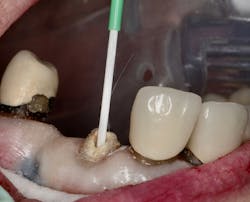

Figure 2: Intaglio surface of existing PFM retrofit preparation

The intaglio surface of the PFM crown contained the preexisting dentin core preparation. The decision was made to prepare the surface to receive the intraoral portion of the post rather than completely remove the remaining dentin (figure 2). This was done to facilitate a smooth retrofit between the remaining root structure and intaglio crown surface as well as to maximize bonding surface area between segments.